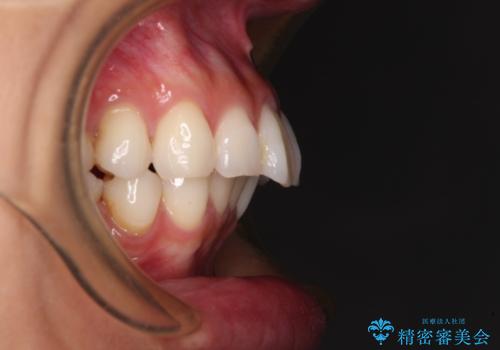

- 飛び出した前歯を気にして来院された患者様です。

口元を引っ込めるために上下左右の第一小臼歯4本を抜歯することとしました。

途中妊娠と出産がありましたが、予定よりも早く治療を終えることができました。